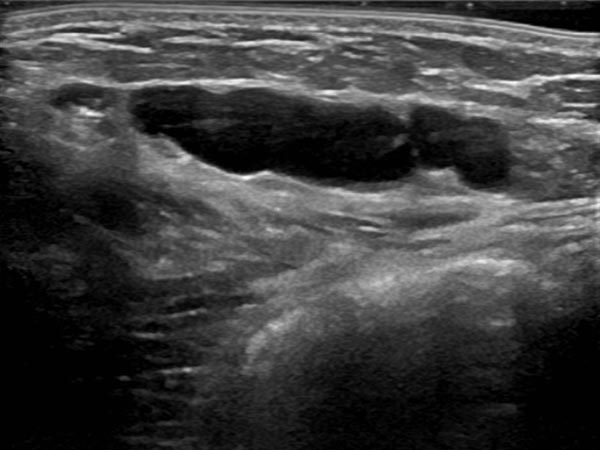

Umschriebene, makrozystische Malformation an der Bauchwand im Ultraschall. Beachte die echofreie Flüssigkeit in den mit Lymphe gefüllten, dünnwandigen zystischen Räumen.

Ultraschall der Bauchwand, etwas weiter kaudal. Hier sind die zystischen Anteile der Lymphatischen Malformation kleiner. Die Läsion liegt jedoch weiterhin extraperitoneal.